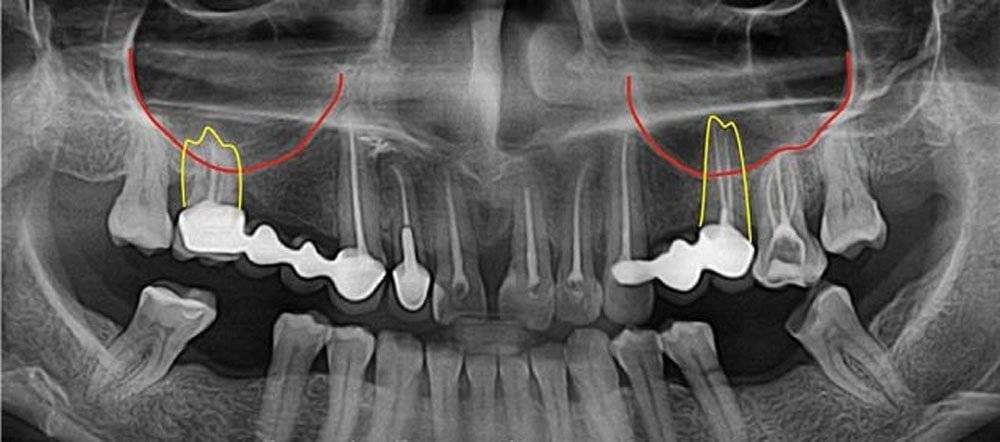

Анатомия: Межкорневая костная перегородка